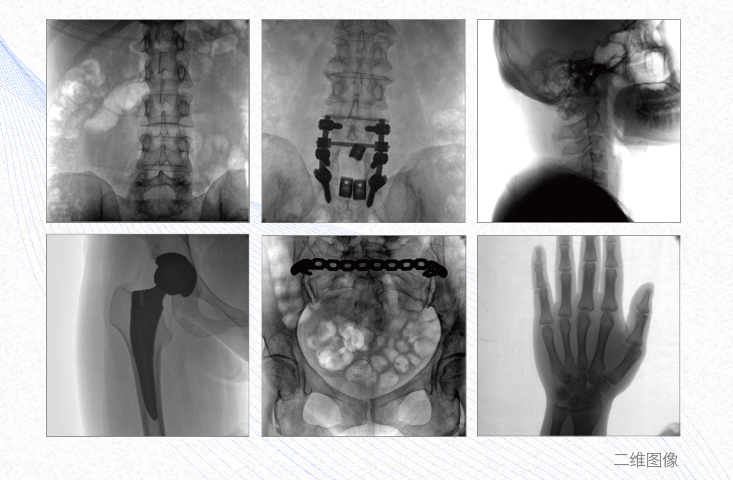

1、脊柱外科

有效重建復(fù)雜的脊柱三維模型,提供準確的二維、三維圖像,提高螺釘植入的準確性,縮短手術(shù)時間,減少并發(fā)癥的概率,降低輻射的攝入。

2、創(chuàng)傷外科

例如骨盆骨折內(nèi)固定術(shù),可術(shù)中三維重建髖臼關(guān)節(jié)面,準確定位并植入螺釘,有效縮短螺釘植入的時間和透視暴露時間,減少術(shù)中及術(shù)后并發(fā)癥發(fā)生的概率。

3、關(guān)節(jié)外科

主要應(yīng)用于肩關(guān)節(jié)、肘關(guān)節(jié)、髖關(guān)節(jié)、膝關(guān)節(jié)的關(guān)節(jié)置換及解剖復(fù)位的定位。它可以準確地置入假體,減少輻射時間,降低輻射劑量。

4、截骨矯形外科

例如治療先天性脊柱側(cè)后凸畸形,可有效引導(dǎo)術(shù)者植入后路螺釘并切除半錐體,達到滿意的截骨矯正效果。